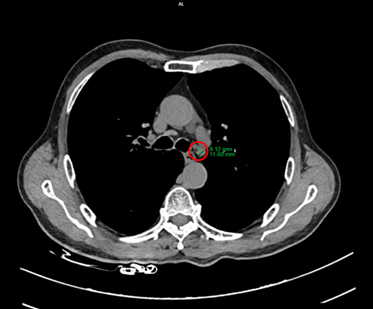

Hình 2: Hình ảnh hạch trung thất ở cửa sổ chủ phổi (vòng trong màu đỏ), kích thước 8x11mm, mất cấu trúc rốn hạch